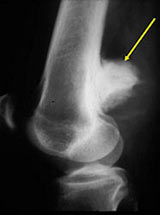

- Posterior distal femur metaphysis (65%)

- Presents as a mass in popliteal fossa

- Lobulated and ossified exophytic mass (cauliflower-like) adjacent to the cortex; attached to metaphyseal cortex via a broad base

- Centrally, the tumor is radiodense (demonstrates ossification)

- The underlying cortex may be thickened

- There is no periosteal reaction since the tumor comes from the outer layer of the periosteum and therefore does not elevate the periosteum.